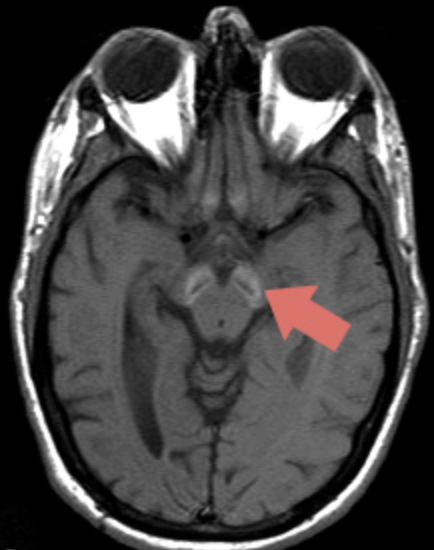

T2-weighted MRI brain imaging of a patient reveals the scan pictured adjacent. The patient is a 36-year-old woman who presented to the emergency room with recurrent episodes of unilateral arm and leg weakness and numbness with gait instability. The treatment of first choice in this case would be:

A. Intravenous ceftriaxone administration

B. Intravenous immunoglobulin therapy

C. Plasmapheresis

D. Sublingual aspirin and intravenous heparin therapy

E. Intravenous corticosteroid therapy

F. Ice cold showers

What is E?

The clinical picture and scan are classic for MS. The MRI scan reveals numerous subcortical white matter demyelinating lesions that are typical of MS. The lesions would be expected to enhance with gadolinium contrast early on during an attack and enhancement can persist up to 8 weeks following an acute attack. The treatment of an acute attack is generally with intravenous corticosteroids for 3 to 7 days. This may or may not be followed with a 1- to 2-week oral prednisone taper. Antibiotics such as ceftriaxone have no place in MS. Intravenous immunoglobulin therapy and plasmapheresis are treatments for MG and Guillain–Barré syndrome and not for MS. Aspirin and heparin therapies are generally instituted in the emergency room setting for acute ischemic stroke when recombinant tissue plasminogen activator cannot be given.